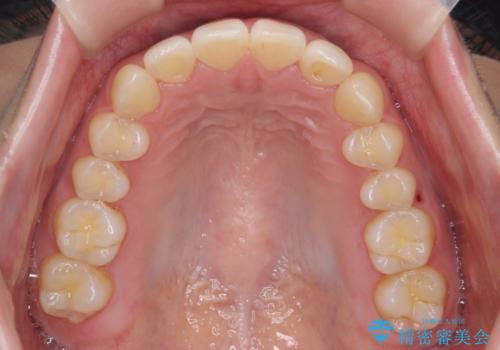

インビザラインのマウスピースではめる装置で歯を引っ張り出すことは難しいと説明し、下の前歯だけワイヤー部分矯正を行ってからインビザライン矯正で仕上げをしました。

周りには気にしなくていいのではと言われていたが、やってよかったと非常に満足されていました。

難しい部分を短期間ワイヤー矯正を行ってからのインビザラインは、全体治療が短くなるだけでなく、仕上がりもよくなるのでオススメです。